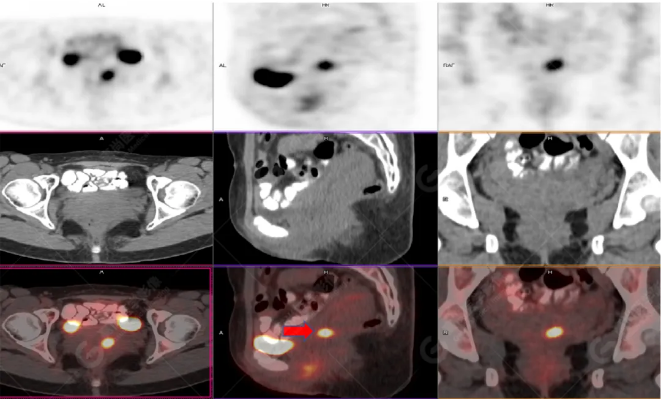

女性 67歲 因背痛查體,糖尿病11年。腫瘤標(biāo)記物:CEA 6.4↑,AFP、CA125、CA199正常。外院MR檢查:胸11椎體-附件左份異常信號(hào),增強(qiáng)環(huán)狀強(qiáng)化,骨原發(fā)?轉(zhuǎn)移?感染?PET/CT影像圖

胸椎溶骨性骨質(zhì)破壞,F(xiàn)DG環(huán)狀代謝增高,SUVmax為4.0。

左側(cè)乳腺一軟組織結(jié)節(jié),F(xiàn)DG代謝增高,SUVmax為2.6。

最終診斷:左側(cè)乳腺癌伴胸椎單發(fā)骨轉(zhuǎn)移。